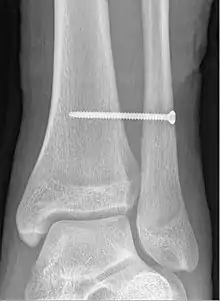

X-ray of a syndesmotic screw in place.

A syndesmotic screw is a metal screw designed to replace the syndesmosis of the human body, usually temporarily. If the syndosmosis is torn apart as result of bone fracture, surgeons will sometimes fix the relevant bones together with a syndesmotic screw, temporarily replacing the normal articulation.

A syndesmotic screw designed to replace the inferior tibiofibular articulation that fix the tibia and fibula together at the lower joint, is 5–6 cm long and made of a stainless, solid metal.